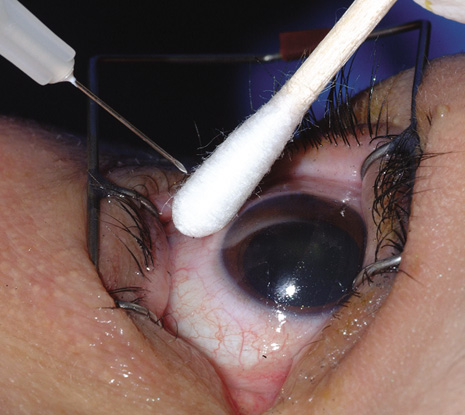

Endophthalmitis after intravitreal injection (Fig. 16) is an uncommon complication that has become the focus of attention in recent years as the use of intravitreal triamcinolone acetonide and various anti-angiogenesis medications have become available (Table 2). It is important to distinguish infectious endophthalmitis from a noninfectious pseudohypopyon caused by triamcinolone acetonide crystals (Fig. 17). Another modality, pneumatic retinopexy, is also rarely associated with the development of endophthalmitis. In the multicenter clinical trial on pneumatic retinopexy, one patient out of 103 eyes in the pneumatic retinopexy group developed endophthalmitis. A total of three endophthalmitis cases have now been reported following pneumatic retinopexy.115–117 The most common isolate is S. epidermidis and treatment approaches include standard intravitreal antibiotic injection as performed in postsurgical endophthalmitis. Strategies to reduce the risk of endophthalmitis include using a povidone-iodine ocular preparation (Fig. 18), using a lid speculum (Fig. 19), and avoiding needle contact with the lid margins and lashes (Fig. 20).

Fig. 18. A povidone-iodine preparation is used to prepare the eye for an intravitreal injection.